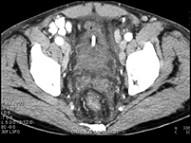

男,45岁,尿频、尿急、尿痛1月余,请根据所示图像,选择最可能诊断 ( )A、膀胱癌B、膀胱炎C、膀胱结石D、膀胱息肉E、膀胱血块

问题 男,45岁,尿频、尿急、尿痛1月余,请根据所示图像,选择最可能诊断 ( )

选项 A、膀胱癌 B、膀胱炎 C、膀胱结石 D、膀胱息肉 E、膀胱血块

答案 B